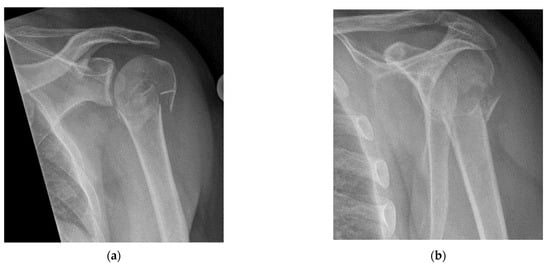

- Quick exclusion of fractures in shoulder dislocations for timely reduction (Figure 13).

- Recommendation 6: Ultrasound should be integrated into the assessment and management of shoulder injuries, including proximal humerus fractures, shoulder dislocations, and post-relocation maneuvers, both prehospitally, in emergency departments, and other acute care settings.

- Example: Suspected left shoulder dislocation

- Integrated into the assessment and management of shoulder injuries, including proximal humerus fracture, shoulder dislocation, and post-relocation maneuver, both pre-hospital and in emergency department settings.